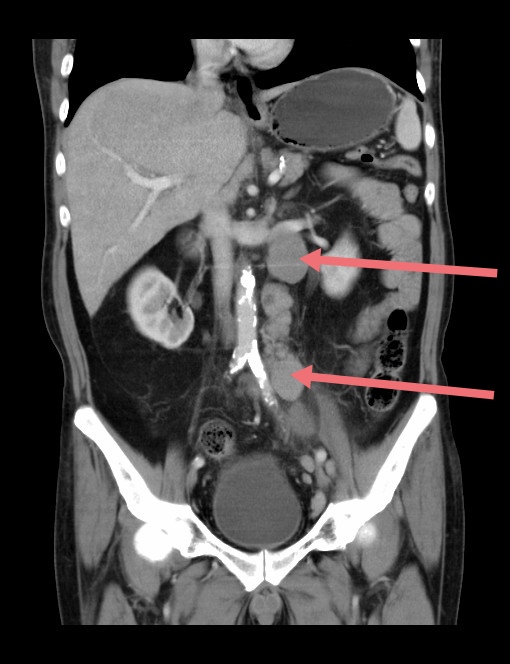

腹腔深部包块CT横断面图像

腹腔霍奇金淋巴瘤CT横断面图像